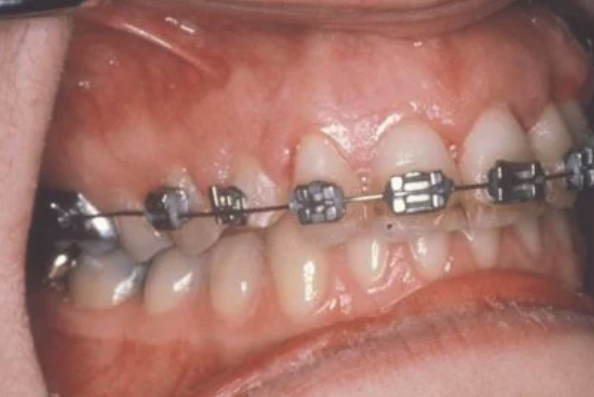

The goal is to erupt the impacted tooth and not to extract it. Once the tooth has moved into its final position, the gum around it will be evaluated. In some circumstances, there may be some minor “gum surgery” required.

In cases where the eyeteeth will not erupt spontaneously, the orthodontist and oral surgeon will work together to get these teeth to erupt. Each case must be evaluated on an individual basis, but treatment will usually involve a combined effort between the orthodontist and the oral surgeon. The oral surgeon will expose and bracket the impacted eyetooth.